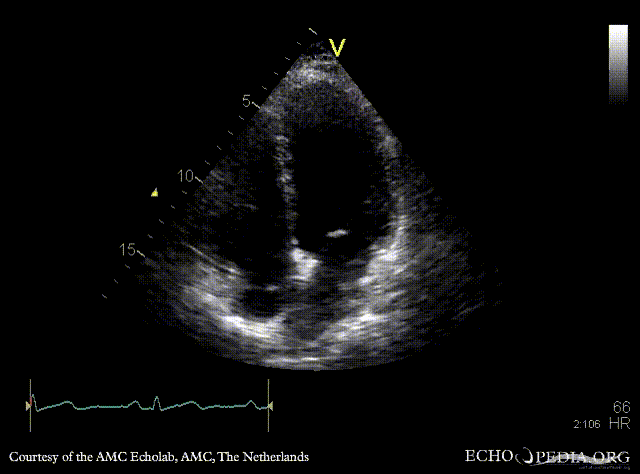

Contrast echocardiogram

AMC Echolab, AMC, The Netherlands

A4CH with contrast: right to the left shunt